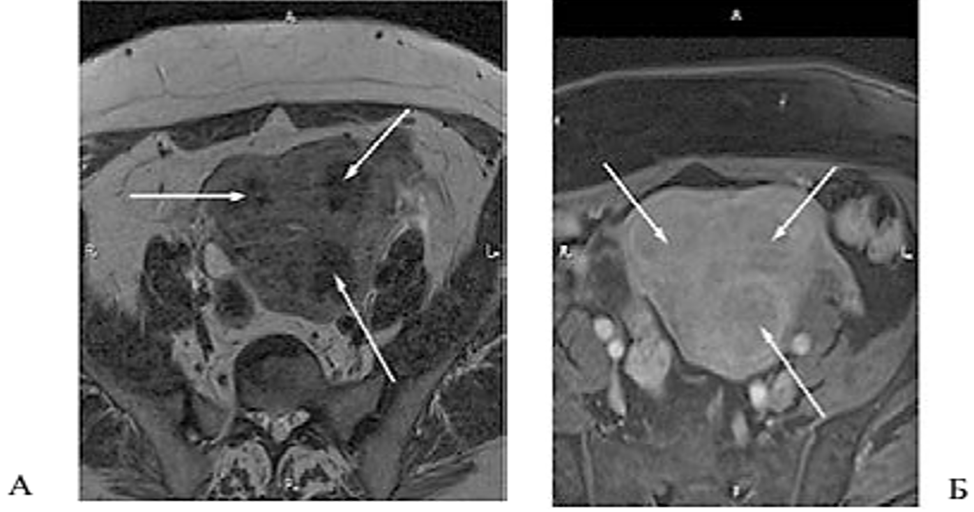

Рис. 1. Больная Н., 58 лет. Множественные лейомиомы матки. Аксиальные срезы через тело матки. А.Т2-ВИ; Б.Т1-ВИ с жироподавлением после введения контрастного препарата. Стрелками указаны лейомиомы матки с признаками гиалиновой дегенерации, характеризующиеся гипоинтенсивным МР-сигналом на Т2-ВИ (А), при введении контрастного препарата (Б) определяется его умеренное равномерное накопление узлами с образованием гиперинтенсивного ободка по периферии образований — псевдокапсулы.